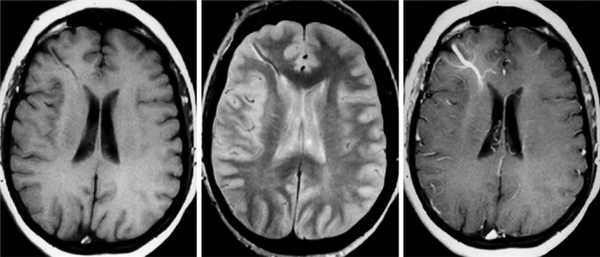

При проведении МРТ в стандартных режимах признаки тромбоза синусов ТМО выражаются в повышении интенсивности сигнала в режимах Т1 и Т2, а также T2-FLAIR. Признаками тромбоза церебральных ВС при КТ являются симптом «шнура» и симптом «пустой дельты» (дефект наполнения в области слияния синусов). КТ и МРТ позволяют выявлять отек мозга и очаги некротических изменений в ткани мозга, что имеет исключительно важное значение для адекватной оценки клинической ситуации и принятия решения о необходимости экстренных мероприятий в пределах острого периода тромбоза, например проведения тромболитической терапии [5, 7, 9, 10].

Данные МР-веносинусографии соответствуют результатам рентгеноконтрастной ангиографии и спиральной КТ-ангиографии [26]. В соответствии с феноменами in-flow (во время потока) и phase-shift (фазового сдвига), влияющими на МР-сигнал, существуют два принципиально разных способа получения изображений: time-of-flight (времяпролетное TOF) и phase-contrast (фазо-контрастное PS) соответственно. При выявлении аномалий синусов ТМО обязательно оцениваются синусы на контрлатеральной стороне в качестве основного источника компенсации. При тромбозе синусов ТМО наблюдается отсутствие сигнала кровотока. Ультразвуковые технологии позволяют также визуализировать и оценивать количественные параметры кровотока по МВ и ВС. Признаком тромбоза верхнего сагиттального синуса является увеличение скорости кровотока по базальным венам и прямому синусу. При тромбозе прямого синуса или синусного стока регистрируется ретроградный кровоток по базальным венам [27]. У пациентов с тромбозом поперечного синуса при транскраниальном дуплексном сканировании выявляется асимметричный кровоток или отмечается отсутствие сигнала кровотока, что может соответствовать гипоплазии поперечного синуса или его тромбозу [28].